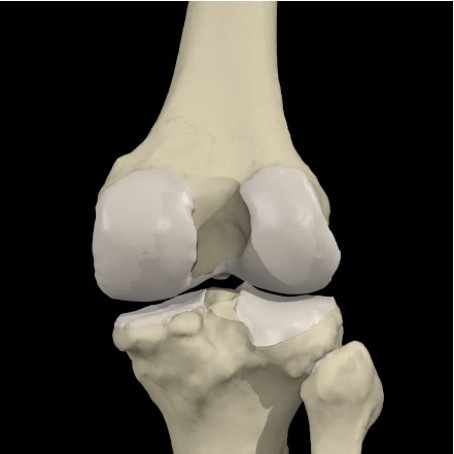

What type of joint is the knee ?

Synovial joint

What are the three main bones to the knee ?

Synovial:

Femur

Patella

Tibia

(Fibula)